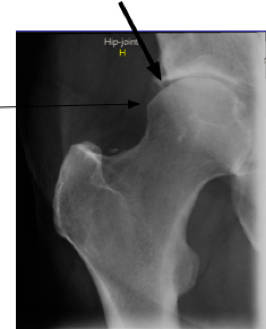

The xray above is of one of his hips. The other is very similar.

Femoro acetabular impingement syndrome case file will make for interesting reading if you or your child have groin pain. It comes in two forms and usually they coexist in the so called mixed form. The spur on the rim of the hip socket is called the pincer. The other is a bump on the neck of the hip; it's known as a CAM deformity.

Femoro acetabular impingement syndrome case file comes in two forms; with pincer and cam deformities.

Mixed type CAM and PINCER

The arrows clearly indicate that he has both the CAM and PINCER type of femoro acetabular impingement syndrome. What is noteworthy is that there is minimal hip degeneration. Slight loss of joint space but no erosions or cysts, no laying down of calcium in the roof of the acetabulum, and a nice smooth surface of the ball of the femur.